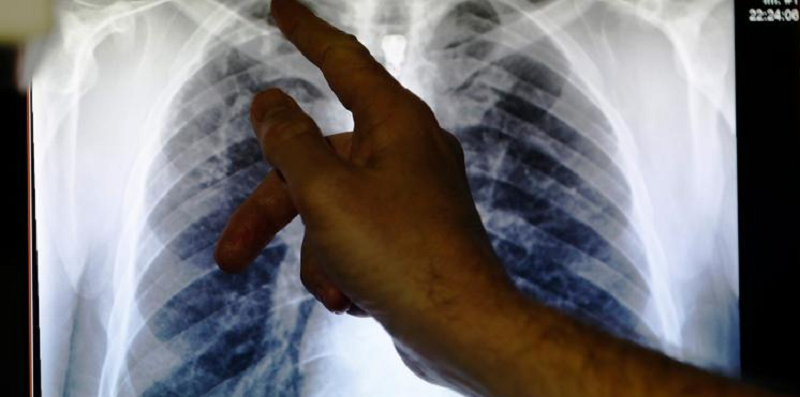

(Foto:REUTERS / Luke MacGregor)Falta de informação e conscientização sobre o tema seriam os motivos